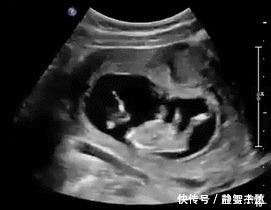

文章插图